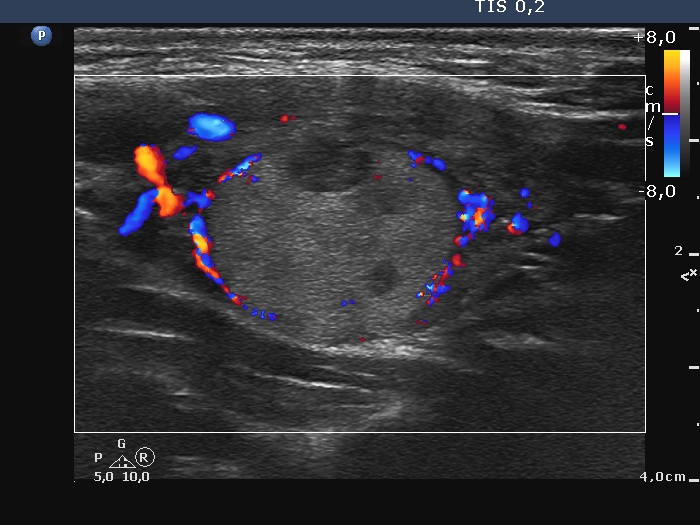

First examination (first row of images)

Clinical presentation: A 20-yr-old woman was referred for ultrasound examination. An elevated aTPO level was detected on evaluation of dysmenorrhea.

Palpation: Both lobes were firm. The left lobe was suspicious having a nodule.

Laboratory tests: TSH 2.08 mIU/L, FT4 13.2 pM/L, aTPO > 1300 U/mL.

The dimensions of the nodule in the left lobe were 18x17x22 mm, width, depth, length, respectively, the volume of the lesion was 3.5 mL.

The patient did not consent to aspiration cytology.